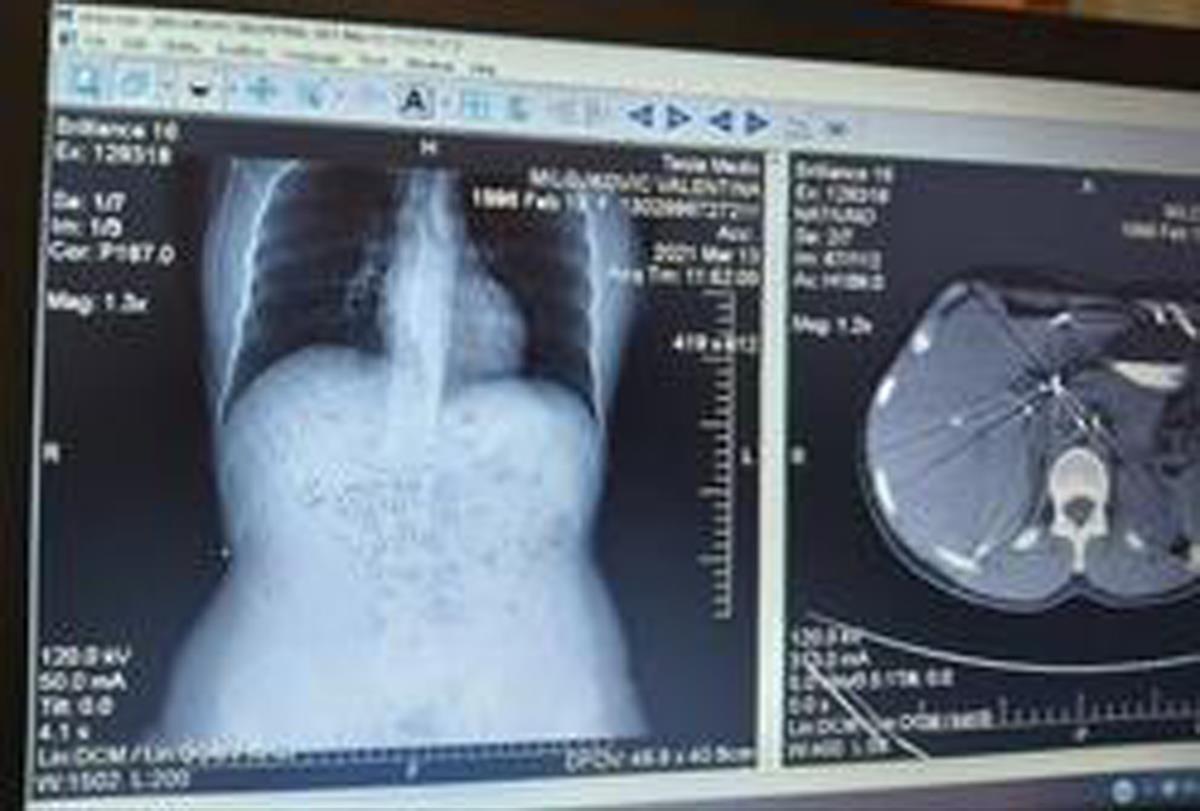

BIVŠI ME JE UPUCAO KRATEŽOM! Operisano mi je 12 ORGANA, IZVAĐENA 4 REBRA! Valentina je 1 u milion koja OVO PREŽIVI!